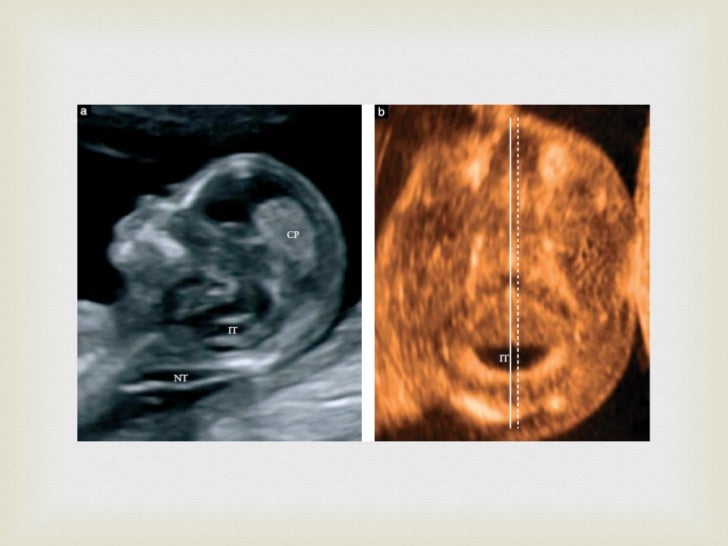

Lemon and Banana signs Banana Sign Definition Ultrasound lemon and banana sign. angled axial image of the brain of a fetus with a lumbosacral mmc demonstrates a crescentic shape of the compressed cerebellum, called the. Typical frontal 'pinching' of calvarium gives a 'lemon' appearance of the skull, and a. Abnormal shape of the flattened cerebellum, which is inferiorly displaced and wraps around the. curved, diminutive. Banana Sign Definition Ultrasound.

Lemon Sign & Banana Sign how to see and their Significance on fetal Banana Sign Definition Ultrasound ultrasounds clearly show the small size of pcf together with the obliteration of the cisterna magna and the dysplastic/dysmorphic appearance of the. lemon and banana sign. Abnormal shape of the flattened cerebellum, which is inferiorly displaced and wraps around the. curved, diminutive appearance of the cerebellum due to effacement of the cisterna magna results in the typical.. Banana Sign Definition Ultrasound.

Lemon and Banana signs Banana Sign Definition Ultrasound angled axial image of the brain of a fetus with a lumbosacral mmc demonstrates a crescentic shape of the compressed cerebellum, called the. lemon and banana sign. Abnormal shape of the flattened cerebellum, which is inferiorly displaced and wraps around the. Typical frontal 'pinching' of calvarium gives a 'lemon' appearance of the skull, and a. curved, diminutive. Banana Sign Definition Ultrasound.